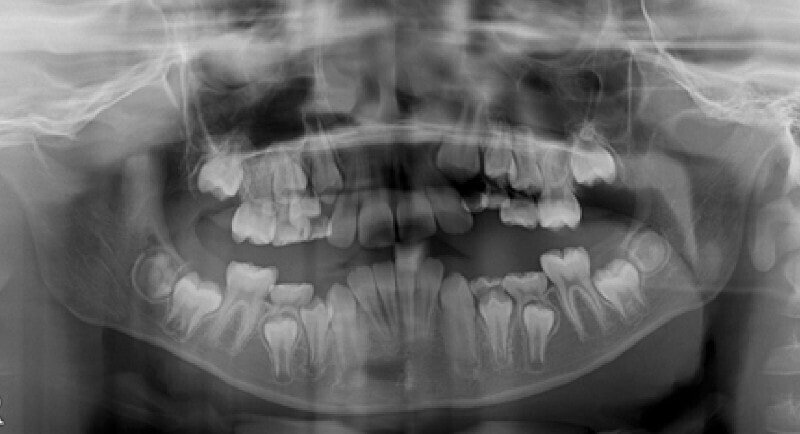

最診断時のセファロ分析:

リケッツ分析の統計上、男児は18才まで顔面の成長があるので、それまで経過観察を行いました。

検査時に予測した通り、骨格的下顎前突の要素はあまり発現しないで済みました。一期治療で反対咬合を解消しておいたことと、舌などの機能訓練に真面目に取り組んでいただけたことも良い要因であったと思います。

外科矯正も回避できて、さらに非抜歯で本格矯正を行うことができると診断し、現在2期治療中です。

下顎前突症例によくある顕著な顔面非対称もなく、幅径も良好な状態です。

少し大臼歯の傾斜が認められます。

上顎8番は先天欠如、下顎8番は埋伏しております。

歯根のパラレリング(平行性)も悪くなく、上顎洞、顎関節にも異常所見はありません。

セサモイドボーンも認められ、家族歴からも、今後の旺盛な下顎の成長の恐れがないと思われる所見です。